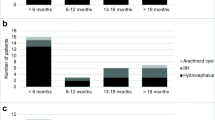

Between February 2016 and October 2018, 17 patients were included in this study. The mean age of the six female and ten male patients was 57 years (26–80). Eleven patients were included with spontaneous SAH and six patients with ICH with ventricular hemorrhage. One patient died in the intensive care unit (ICU) before and had to be excluded. 16 data sets were analyzed.

In all patients an EVD was placed. In eight patients a NEUROVENT®-P-tel probe was implanted within the same session. Eleven of the 16 patients developed a secondary hydrocephalus and required VPS implantation: all patients of “P-tel + EVD group” (n = 8) and three of “EVD group” (Fig. 2). In these patients a VPS with sensor reservoir® was implanted through a left frontal burr-hole while the NEUROVENT®-P-tel probe was implanted contralaterally in those that did not already have one (Fig. 2).